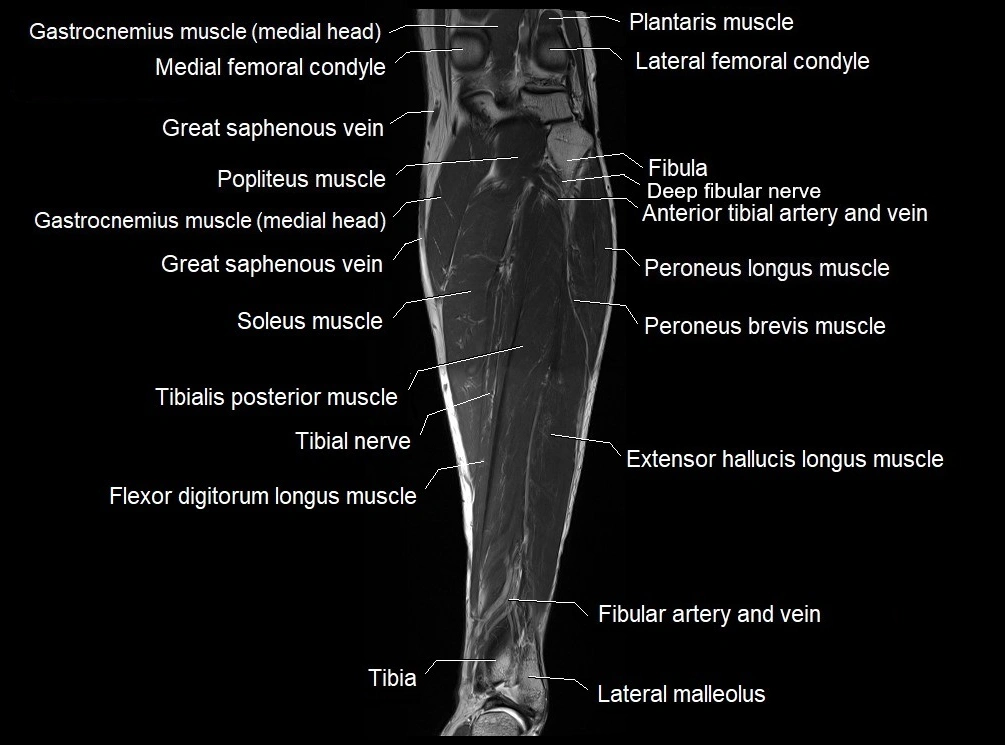

MRI image